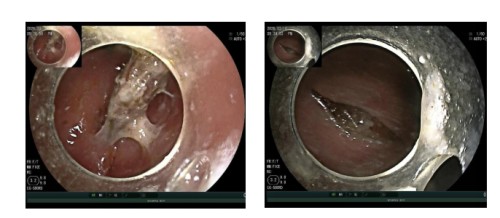

接诊后,内镜中心迅速为患者进行了胃镜检查。镜下所见让在场的医护人员都捏了一把汗:一枚长约2.5厘米、两端尖锐的枣核正崁顿在胃窦部。由于枣核两头细长如针,随着胃部的蠕动,一旦进入十二指肠,极易引发肠穿孔、腹膜炎等致命并发症。

王志斌主任凭借丰富的临床经验和精湛的内镜操作技术,用圈套器先将枣核套住拖至胃体,改用异物钳精准夹住枣核的一端,调整角度使其长轴与食管腔平行,内镜中心王爽、马广雨护士密切配合王主任的操作,小心翼翼将其从胃内顺利取出。整个过程操作流畅,患者消化道黏膜无活动性出血,术后患者生命体征平稳,在场所有人悬着的心终于放了下来。